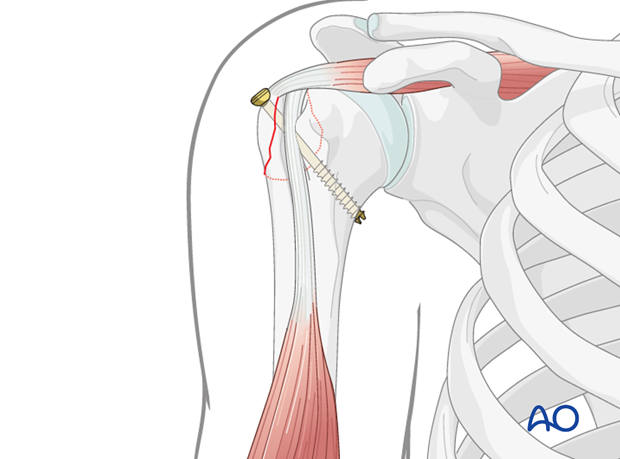

Fixation with Screws

Screw fixation relies on adequate bone stock in both the fragment and the humeral head. The choice of screws depends on fragment size and bone quality.

1. Principles of Screw Fixation:

* Lag Screw Principle: The primary goal is to achieve interfragmentary compression across the fracture line. This is accomplished using partially threaded screws where the threaded portion engages the far cortex (or cancellous bone within the humeral head), and the unthreaded portion slides through the near cortex (GT fragment). As the screw is tightened, the fragment is pulled towards the humeral head, creating compression.

* Small fragment cortical screws: Typically 2.7 mm or 3.5 mm diameter, either partially or fully threaded.

* Headless compression screws: Increasingly popular for GT fractures, especially for fragments that are large enough to accommodate them. They offer the advantage of being countersunk below the bone surface, minimizing soft tissue irritation and potential impingement, while providing excellent compression. Common sizes include 3.0 mm, 3.5 mm, or 4.0 mm.

3. Screw Placement and Trajectory:

* Typically, 2 to 4 screws are used, depending on the size and comminution of the GT fragment.

* The screws are usually directed from the superior or posterolateral aspect of the GT into the cancellous bone of the humeral head.

This image illustrates the final screw insertion, providing stable fixation of the greater tuberosity fragment.

- Technique Steps (Lag Screw example):

- Insert Screw: Insert the partially threaded screw and tighten gently to achieve compression.

- Repeat: Apply additional screws (typically 2-4) in a similar fashion.